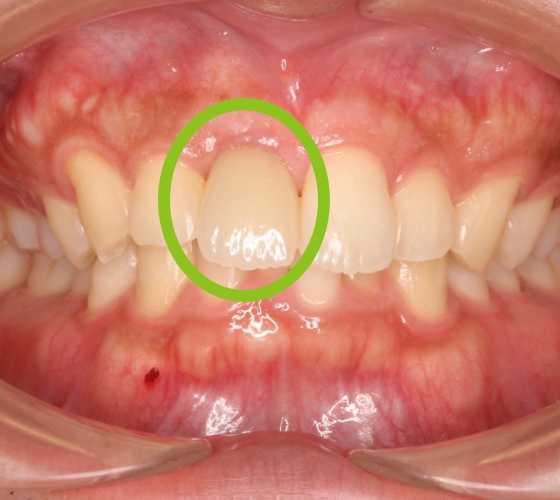

20代男性 上の前歯へのインプラント治療

治療内容 「前歯をきれいにしたい」との主訴で来院されました。

根っこが折れていたため抜歯後、「隣の歯は削りたくない」とのことでインプラント治療を希望されました。

インプラント予定部位の骨が少なく、歯ぐきも痩せていたので、GBR(骨造成)と結合組織移植(歯肉の移植)も施し、審美的な外観を整えました。

自然な感じの仕上がりとなり、患者様は、思いっきり笑うことができるようになりました。

治療期間・回数 治療期間:約10カ月

通院回数:10回程度

治療費用(総額)

560,000

(インプラント440,000円、GBR100,000円、結合組織移植20,000円。時期や手法により異なる場合があります。)